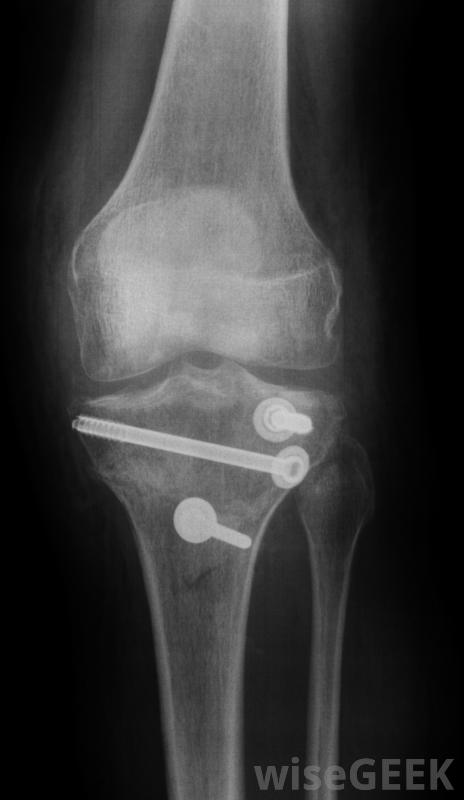

骨鉆是外科醫生用來修復骨折的設備。骨鉆用于制造手術用針和螺釘連接的孔。通過對嚴重骨折的鋼板鉆孔和擰緊,外科醫生能夠挽救許多需要截肢的肢體。骨鉆是由外科級材料制成的,能夠在不影響開放性傷口的情況下進行手術。骨鉆可以幫助挽救原本需要截肢的四肢當把一個銷釘安裝到骨頭上時,外科醫生可能需要鉸出一個孔,以便正確地安裝銷釘。骨鉆能夠輕松地完成這個功能。用更原始的手動工具可能需要幾個小時才能完成,而完成這項工作所節省的時間就是時間病人不需要麻醉,這往往是影響危重病人存活率的一個因素嚴重骨折,外科醫生能夠挽救許多需要截肢的肢體。骨鉆通常是電力驅動的。馬達以驚人的速度運轉,使鉆穿硬骨看起來很容易,這種手術并不僅僅局限于骨折的修復骨髓鉆也用于從骨髓中提取骨髓。骨髓是通過在骨頭上鉆一個小孔取出的。在很多情況下,通過身體的再生能力,這個洞會逐漸被新的骨頭填滿。骨鉆會制造出釘和螺絲固定的孔與手動鉆相比,電動骨鉆有兩個好處。手鉆鉆鉆骨需要更長的時間,這意味著患者失去意識的時間更長。而且,手鉆沒有那么精確。當外科醫生轉動鉆頭時,鉆頭會搖晃移動。這導致了一個長方形的孔。電鉆以快速而精確的方式通過,在骨頭上形成一個精確大小的孔金屬板和螺釘可用于固定橫向骨折,使用骨鉆。孔的精確公差允許螺釘和銷更好地配合,同時促進更快的愈合。由于鋼板和螺釘的更好配合,骨能夠更好地自我修復,并且通常與骨折前一樣牢固或更牢固。其操作機構是密封的,因此能夠輕松消毒。這減少了感染的機會,并保護鉆頭免受任何外部污染骨骼解剖圖。